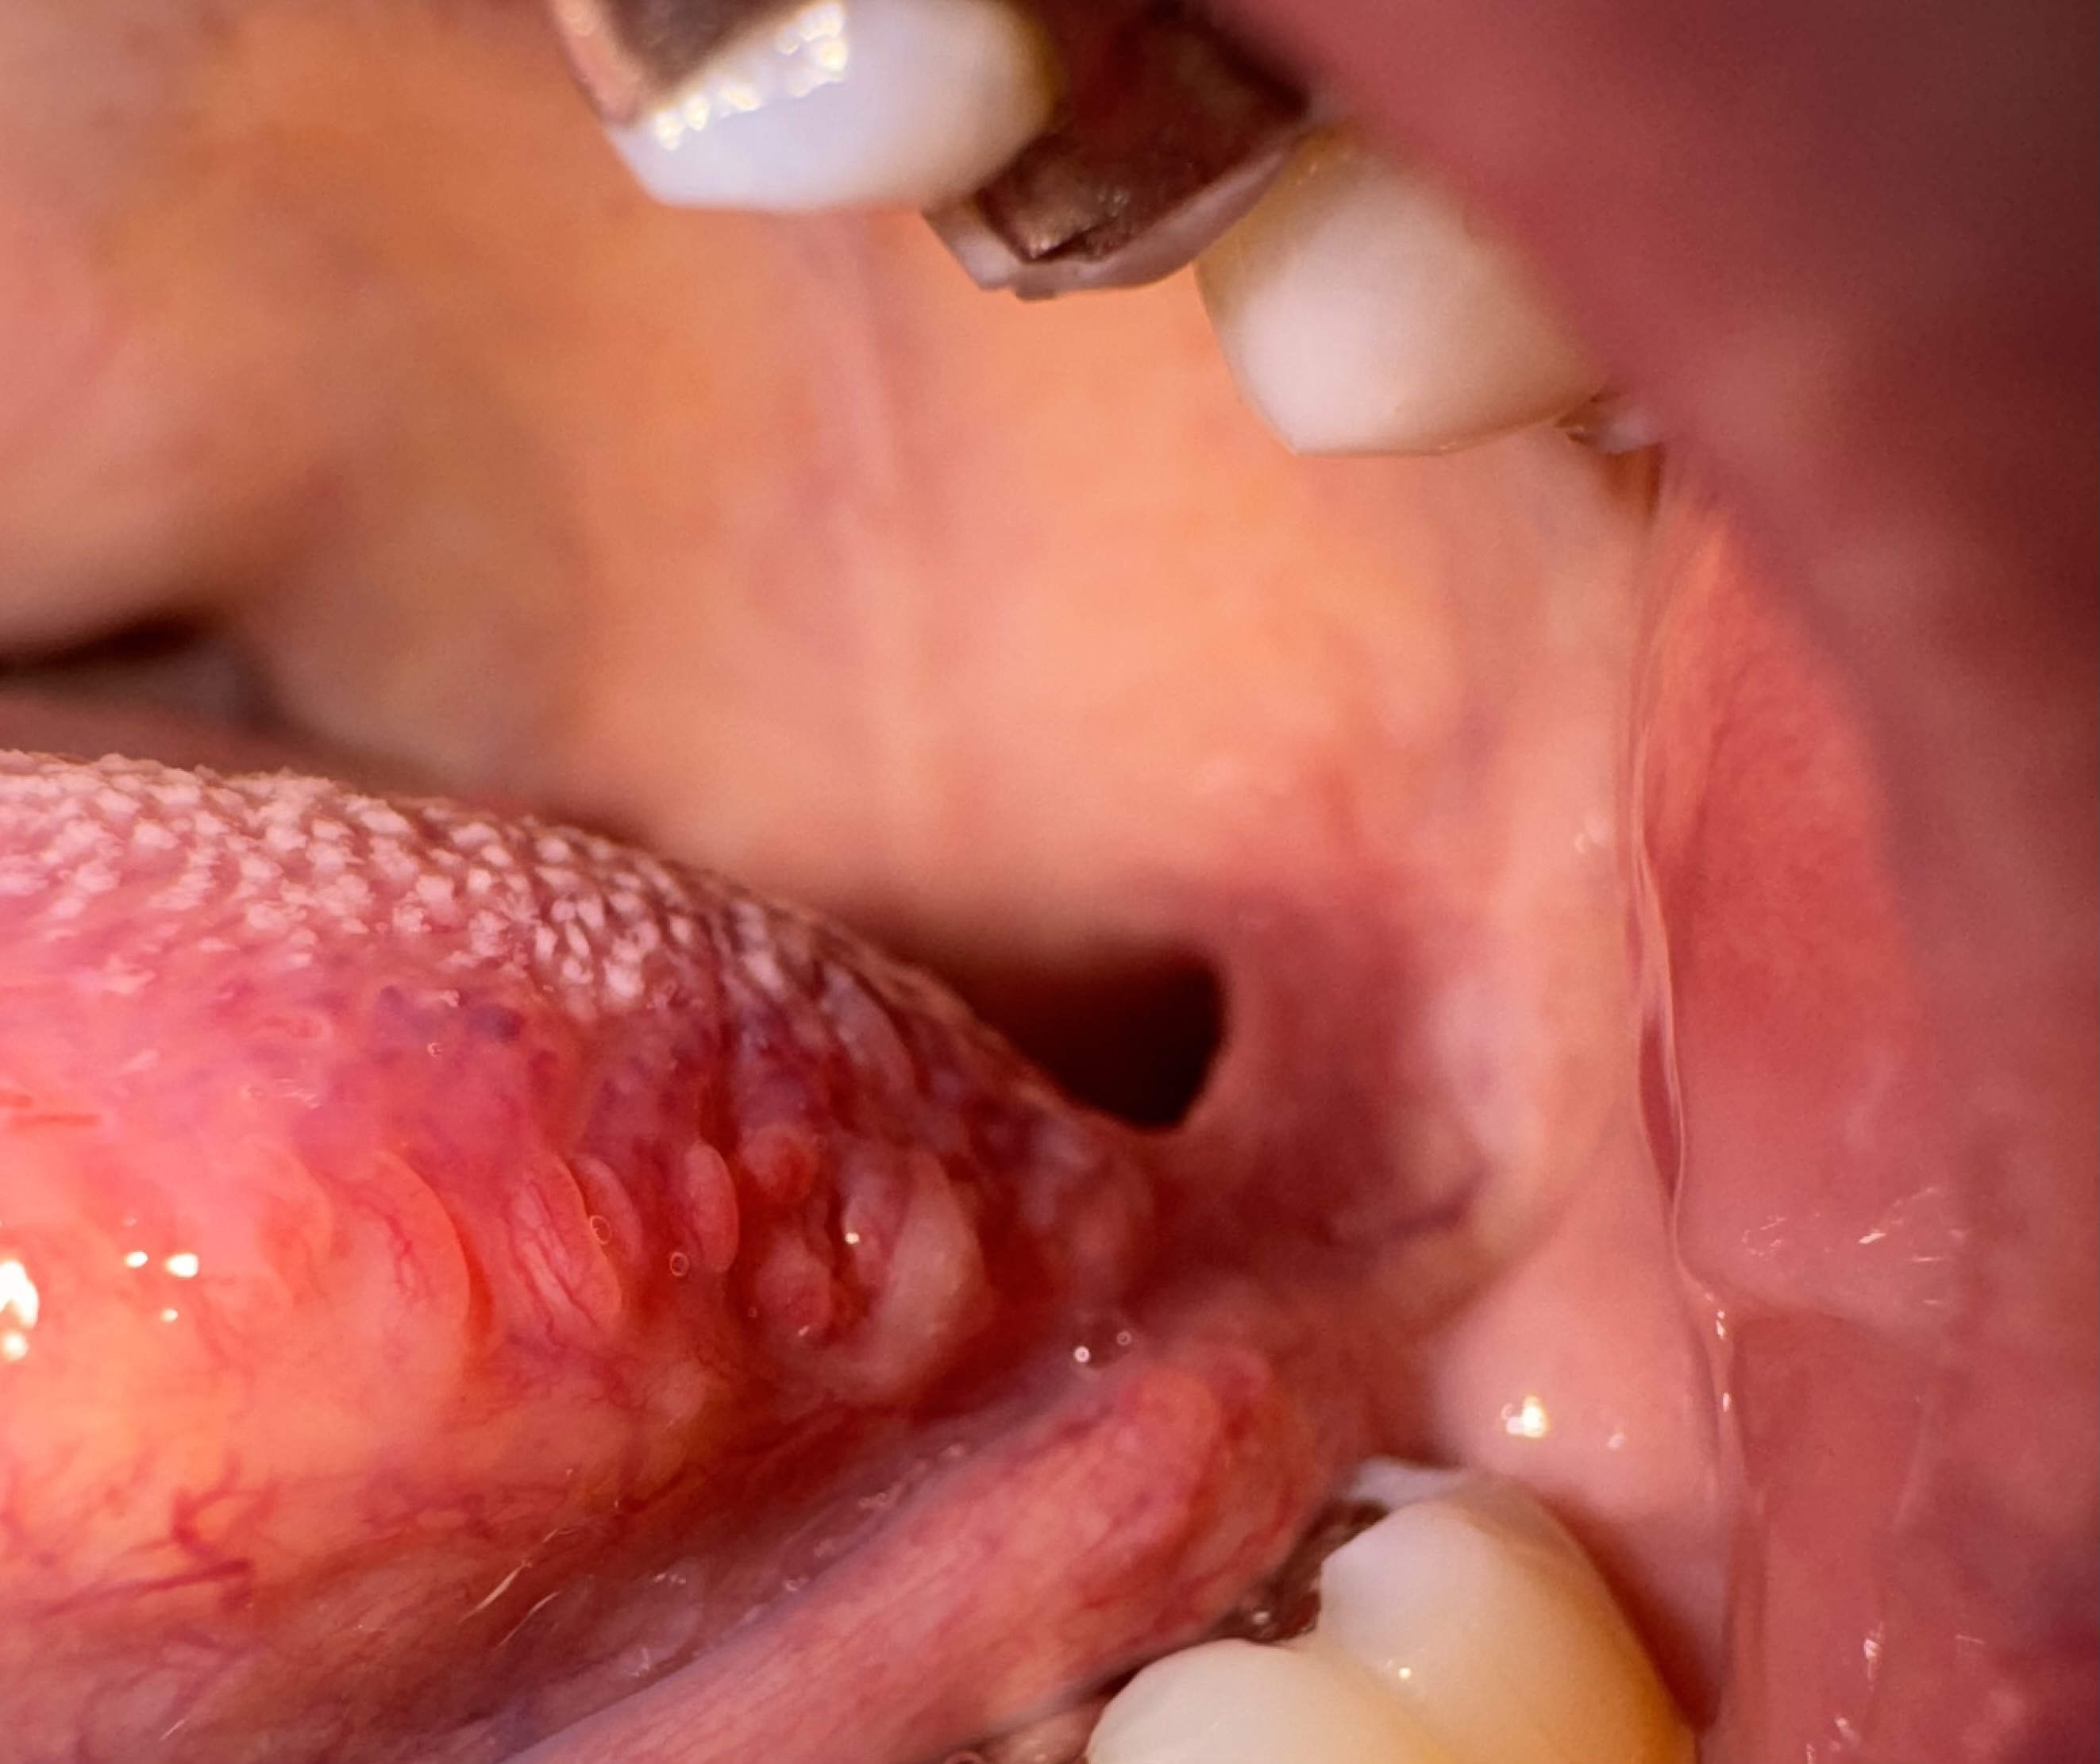

頬の粘膜に口内炎が潰れたような見た目のできものがあります。